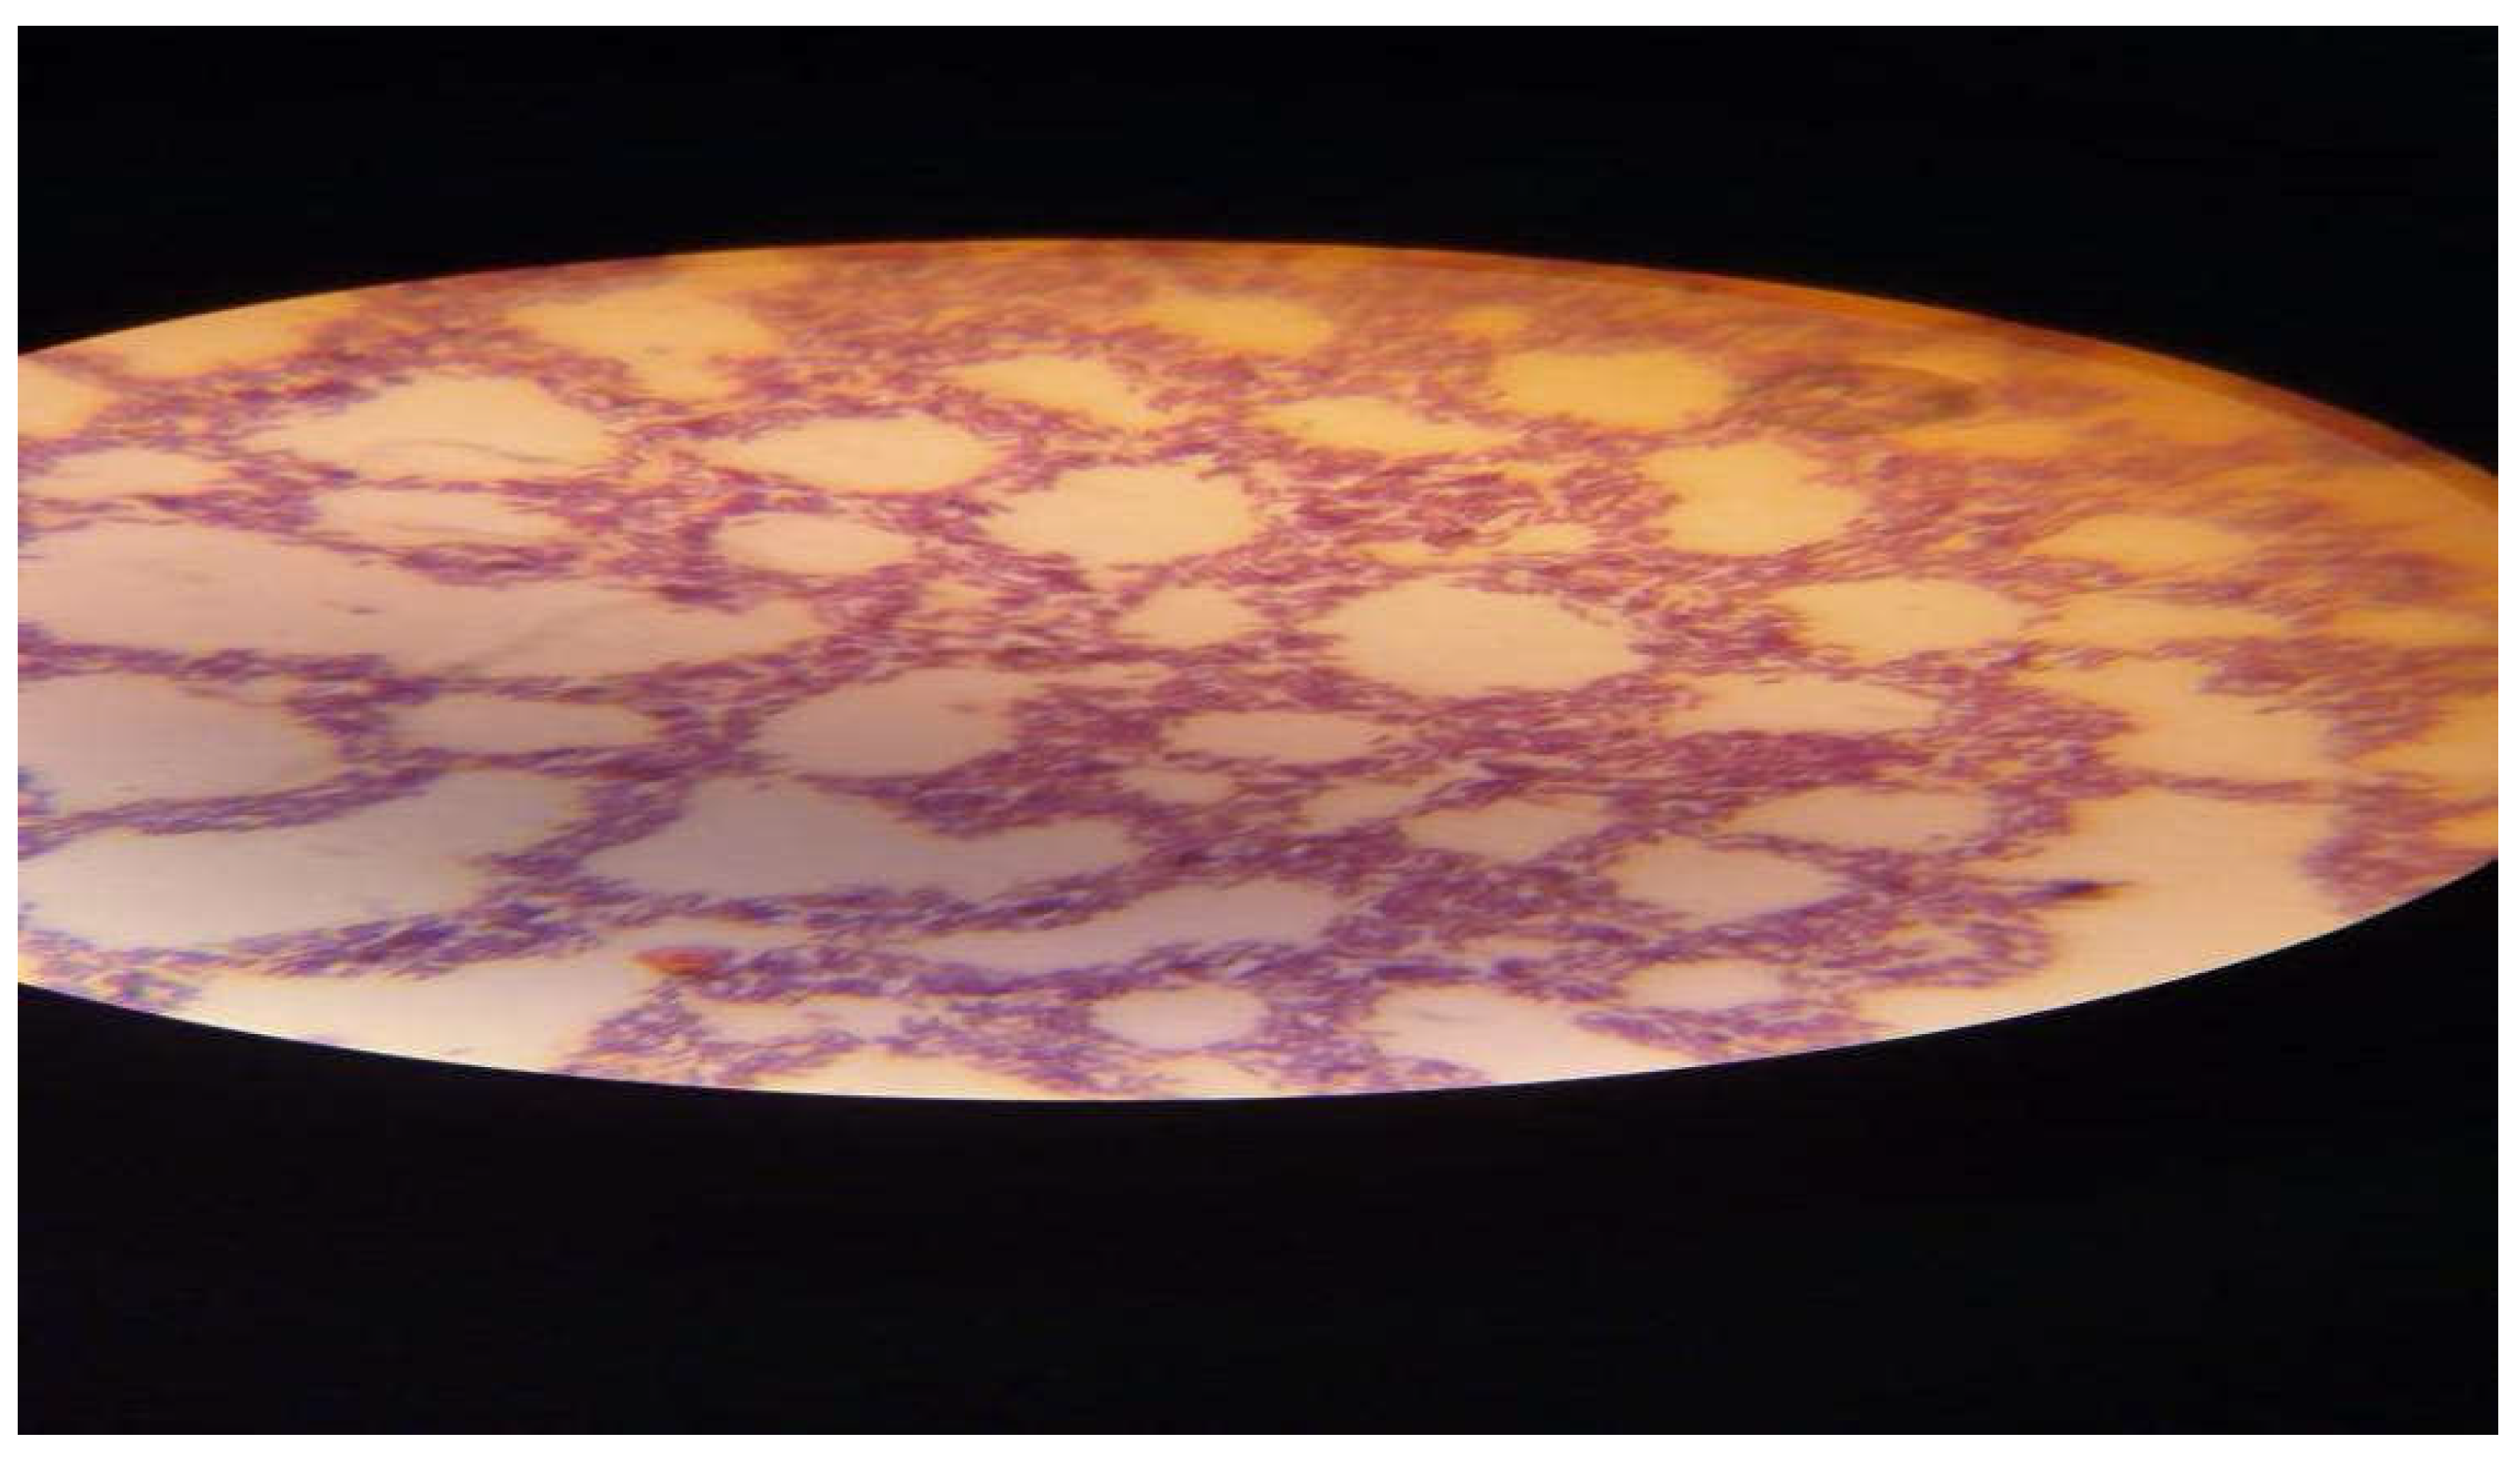

Figure 2. It shows Positive Gram staining of bacterial Bacillus subtilis and cereus isolates producing thermostable fibrinolytic enzymes.

Preprints 103875 g002